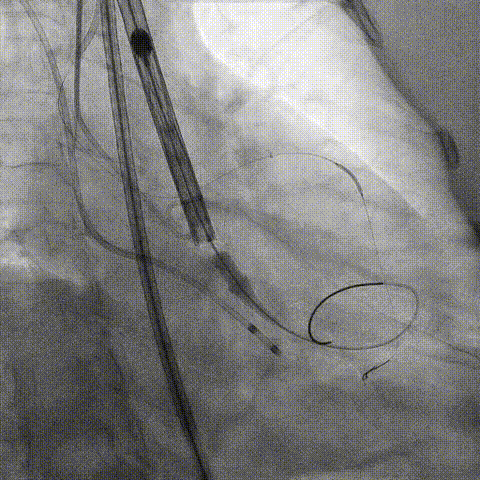

第一次释放

再次评估左冠开口,考虑调整瓣膜深度

回收后调整深度,再次释放

评估左冠开口

左冠开口切线位造影

决定左冠烟囱支架保护冠脉